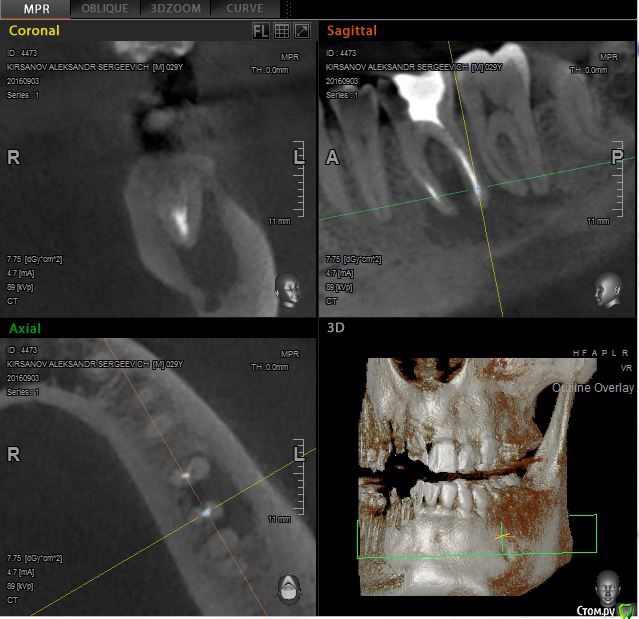

St. Опубликовано 12 ноября, 2016 Поделиться Опубликовано 12 ноября, 2016 Выложу скрины приложенного КТ. Так ответов будет больше. Есть пропущенный канал в 6 зубе. И нужно проверить на жизнеспособность соседний 7. Я бы рекомендовала попробвать перелечить и понаблюдать. Но Вы должны для себя понимать что перелечивание каналов очень сложная, дорогая и непрогнозируемая процедура. Хотя вероятность успеха достаточно высока. Если хотите гарантий - тогда удаление и имплант как восстановится кость. Еще хорошо бы знать как давно лечили каналы в этом зубе, как он вел себя после лечения, беспокоит ли сейчас? 2 Ссылка на комментарий

St. Опубликовано 12 ноября, 2016 Поделиться Опубликовано 12 ноября, 2016 11, 21 по кт без особенностей. Так что артефакты скорее всего. В 23( левый клык) есть тоже воспаление на корне. Нужно планово перелечиавать. Ссылка на комментарий